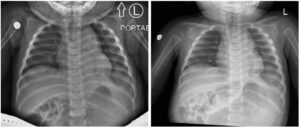

Incarcerated Gastric Volvulus and Splenic Herniation. Chest Radiographs on Postoperative Days 1 and 4. Unannotated. JETem 2025